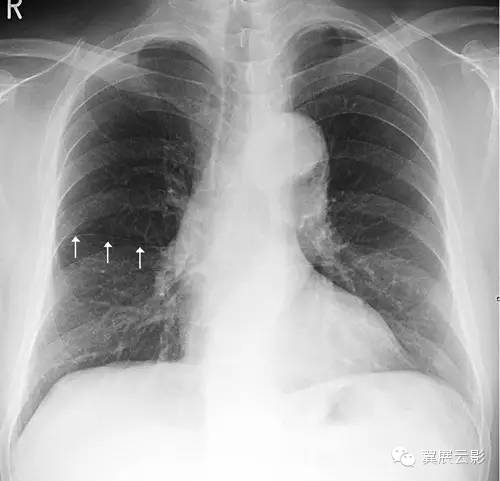

正位胸片常可以看到细线状的右肺水平裂,位于右肺野中部,自肺野边缘向

求助,右肺改变,是炎症,还是水平裂?